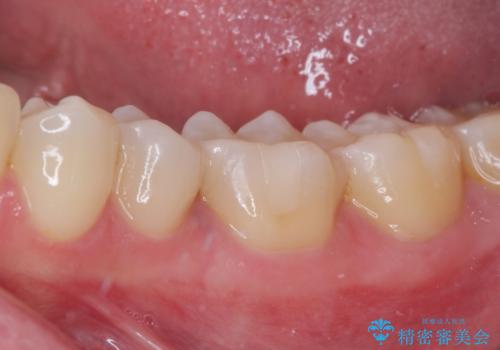

そして次の来院時、セラミックインレーを装着し、噛み合わせなどの調整を行います。

インレーを装着するときは、唾液や血液による接着力の低下を避けるためにラバーダム防湿を行いました。

自然な色調で大変満足されました。